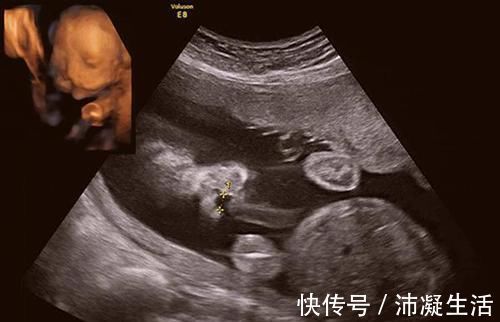

到底什么原因会导致胎儿畸形呢?

二、饮食问题

王女士就是因为饮食问题导致了孩子畸形,所以在饮食问题上要特别注意。提前咨询好医生,清楚什么东西能吃,什么东西不能吃。如果害怕自己忘记可以列个清单,放在醒目的位置以此来提醒自己。在孕期也不能乱吃药。有些药物就有致畸作用,所以在吃药之前需要咨询好医生。